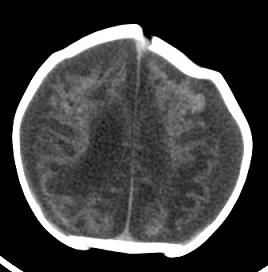

男,4个月大,2个月前无诱因下四肢抽搐、伴呕吐,近2天来抽搐频发,伴发热。查体:双眼疑视,神萎、纳差;颈抵抗,四肢张力高。

病史太长了,原因不好定,不过如果2个月前小儿正常的话可考虑积水型无脑畸形,积水型无脑畸形小儿刚生下来表现可正常,存活一两个月后出现症状.

另不除外缺血缺氧性脑病,感染等改变

2个月前缺血缺氧性脑病留下的后遗症。

脑出血后,软化灶形成了。脑发育不良

支持缺血缺氧性脑病留下的后遗改变(脑软化灶+脑发育不全+双侧慢性硬膜下积液+小头畸形)。

要注意化脓性脑膜、脑炎,硬膜下积脓,脑积水的可能,建议腰穿助诊。